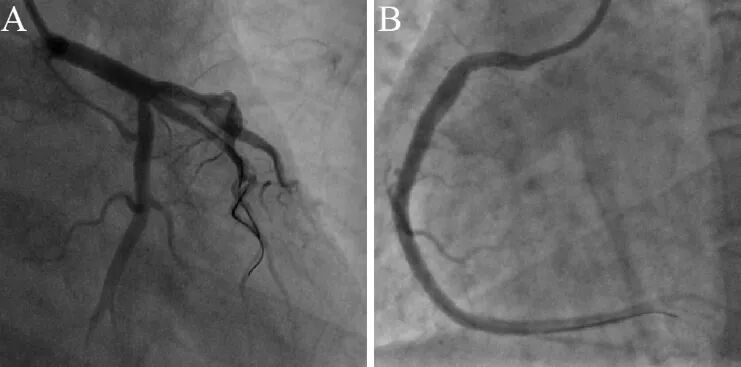

患者入导管室后血流动力学不稳定伴意识模糊,血压50/30mmHg,去甲肾上腺素微泵维持,予气管插管呼吸机辅助通气。经右股动脉植入IABP。最少造影剂、最少体位完成冠脉造影:右冠近段完全闭塞,左主干-前降支近段弥漫性狭窄95%,整个左冠系统血流缓慢(图5)。

图5冠脉造影。A 右冠,B左冠

复查造影冠脉恢复前向血流TIMI3级,整个冠脉血管显著增粗!左主干直径达5-6mm,支架植入位置为左主干-前降支近段-对角支近段(图7A),支架显著偏小。

拟开通右冠病变,SAL0.75指引导管造影到位,造影发现右冠闭塞自行缓解,管径显著性增粗,仅残余近段狭窄30%,前向血流TIMI3级(图7B)。诊断明确为冠脉痉挛!

图7 复查造影冠脉整体性增粗。A左冠,B右冠